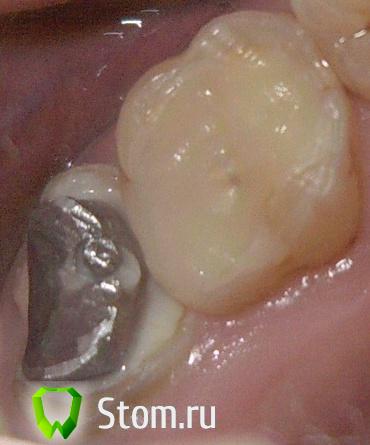

mur-in-law Опубликовано 6 февраля, 2012 Поделиться Опубликовано 6 февраля, 2012 (изменено) Здравствуйте, уважаемые доктора!Сразу к делу. У меня вот такие два верхних моляра (семерка и шестерка).На семерке, как мы видим, стоит металлическая ВКВ. Такую же я хотел бы и на соседней шестерке. А сверху мечтаю накрыть их цельнометаллическими коронками.В шестерке сейчас после мех. и мед. обработке каналов заложено лекарство в корни.Лечащий врач настаивает на том, что ВКВ ставить не целесообразно, так как придется много удалять зубной ткани. Посоветуйте мне пожалуйста, настаивать ли на ВКВ + коронка или действительно лучше обойтись СВШ + коронка, а то и просто поставить композитную пломбу.Керамическую вкладку не рассматриваю, так как это скорее всего дорого.Пломбу ставить уж точно не хотелось бы, так как не хочу рисковать, что "полетит" через несколько лет какая-нибудь стенка и придется опять ремонтировать. Изменено 6 февраля, 2012 пользователем mur-in-law Ссылка на комментарий

mur-in-law Опубликовано 22 февраля, 2012 Автор Поделиться Опубликовано 22 февраля, 2012 2. Пломба + СВШ.4. СВШ + коронка.Какой же мне лучше выбрать? Неужели так никто и не посоветует?Положился целиком и полностью на волю врача и получил: пломба на анкерном штифту+коронка. Правда коронку еще не поставили. Вообщем вотИ теперь меня, конечно, интересует, какая коронка должна больше простоять: на семерке (на ВКВ) или на этой шестерке? Коронки будут делать из хромо-никелевого сплава.И еще вопрос. Как их лучше сделать раздельно или объединить? Ссылка на комментарий

mur-in-law Опубликовано 1 марта, 2012 Автор Поделиться Опубликовано 1 марта, 2012 (изменено) где, что и сколько простоит - сказать невозможно.Спасибо, конечно, но как-то ни о чем...Вот результат сегодняшнего посещения.Обточили. как я понял не только шестерку, но и семерку подправили.Интересно, а что это в центре (указано стрелкой), гуттаперча?Коронки попросил сделать раздельные. Изменено 1 марта, 2012 пользователем mur-in-law Ссылка на комментарий

Vitasem Опубликовано 10 марта, 2012 Поделиться Опубликовано 10 марта, 2012 (изменено) По последнему снимку можно о многом сказать:прилегание вкладки желает лучшего(слой цемента очень большой)обычно перед изготовлением вкладки зуб должен быть обработан полностью, а не сформирована луночка в зубе для изготовления жалезнай палочки(это сказывается на качестве прилегания, а соответственно на качестве всей работы).форма уступов - но это относительноотсутствие временных коронок - без них вообще нельзя изготавливать коронкианкерные штифты вообще нельзя использовать для подготовки зуба к протезированию(в таких случаях я вообще начинаю протезирование с удаления анкера!)десна на предыдущем снимке выглядит куда лучше чем после опиливания (скорее всего доктор тут поиграл в мясника и было много крови)как стоматолог - этому бы доктору свои бы зубы не доверил.если как эконом вариант - то сойдет (хотя экономия зачастую выливается в большие переплаты) Изменено 10 марта, 2012 пользователем Vitasem Ссылка на комментарий